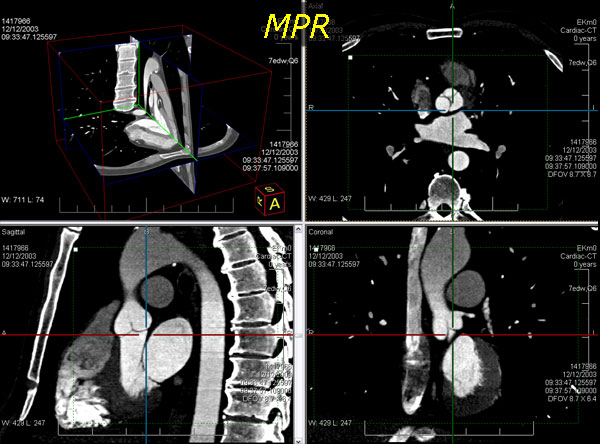

leadtools medical 3d sdk技术简化了二维医学影像切片三维医学可视化的重构技术,如mri和ct栈。leadtools medical 3d sdk技术提供了原始数据的许多不同的替代视图。它使用了三维重构技术如mpr、vrt、mip、minip和ssd,且支持裁剪平面、板、缩放、变焦、相机控制、阈值、透明度和影像处理的投影技术。

通过提供可视化的解剖细节,体数据的检查提高了解释、识别的速度和医师总测试评估的时间,这些仅仅利用二维切片是很难诊断的。

使用leadtools medical 3d sdk技术,开发者可创建使用任意二维横截面切片堆生成三维模型的应用程序。为了生成有意义的三维模型,横截面必须互相平行,因此leadtools提供了使用dicom标签识别、分离和设置体积栈的功能。

同时,leadtools medical 3d sdk提供了一个接口,可定义三维像素(体素)模型,还可通过三维模型的正确测量、方位标注和缩放进行患者定向,并生成斜交切片和正交切片。

向leadtools medical 3d sdk engine添加横截面切片后,开发者通过简单地设置所需的模型类型属性即可在不同的模型类型间转换。leadtools medical 3d sdk engine支持以下的三维模型类型(点击模型类别查看截图):

leadtools medical 3d sdk相机和人眼的功能是一样的,它创建了三维体的一个视图。使用leadtools medical 3d sdk,生成的三维体视图可以被操作。开发者可控制leadtools medical 3d sdk相机在三维空间中变焦、平移和旋转,并可将投影模式设置为正交或透视。不必要或阻塞的骨骼可从视图中移除,只需设置远近切割面,无需从体中移除数据。

leadtools medical 3d控件也能生成斜交和正交的二维mpr切片。通常情况下,一个mpr视图包括显示所需结构的三个正交平面视图和操纵这个体的方法。leadtools?medical 3d控件允许每个生成的二维正交平面(轴向、矢状和冠状)和独立的leadtools medical viewer 控件单元联系在一起。在这个配置中,leadtools?medical image viewer和leadtools medical 3d控件共同提供了交互式的三维光标同步和任意正交平面的支持。

leadtools medical 3d sdk提供了二维正交mpr平面的交互式板控制。当三维体板功能启用时,leadtools medical image viewer控件使用每个二维mpr平面上的虚线矩形显示板的边界。用户可以使用鼠标拖拽曲线调整裁剪平面。